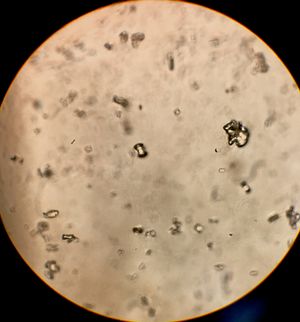

혼탁한 오줌은 세균 감염의 증상일 수도 있지만, 인산칼슘 등의 염이 결정화한 것일 수도 있다.4. 요검사

오늘날 임상 요검사는 소변의 색깔, 탁도 및 냄새를 기록하고, 화학적 분석과 구성 요소를 정량화하는 소변 검사를 포함한다. 요로 감염이 의심될 때 소변의 세균 배양을 실시하며, 증상이 없는 세균뇨는 치료가 필요하지 않다.[32] 소변의 현미경 검사는 유기 또는 무기 기질을 확인하고 진단에 도움이 될 수 있다. 소변의 색깔과 양은 수분 공급 수준을 나타내는 신뢰할 수 있는 지표가 될 수 있다. 맑고 많은 양의 소변은 일반적으로 충분한 수분 섭취를, 진한 소변은 탈수를 의미하지만, 이뇨제를 섭취한 경우에는 소변이 맑더라도 탈수 상태일 수 있다.

요검사는 소변의 색깔, 탁도, 냄새 등을 육안으로 확인하고, pH, 단백질, 당, 케톤체, 빌리루빈, 잠혈 등 화학적 성분을 분석하며, 현미경을 통해 적혈구, 백혈구, 상피세포, 세균, 결정 등을 검사한다.- 육안 검사: 소변의 색깔은 신체의 수분 상태, 약물, 화합물, 음식에 함유된 색소 또는 염료와의 상호작용, 질병 등에 따라 달라진다.[8] 정상적인 소변은 무색에서 호박색 사이의 투명한 노란색을 띤다.[8] 무색 소변은 과도한 수분 섭취를, 진한 노란색 소변은 탈수를 나타낼 수 있다. 붉은색, 갈색, 분홍색, 주황색, 녹색, 푸른색, 보라색, 검은색 등 비정상적인 소변 색깔은 특정 질병이나 약물, 음식 섭취와 관련이 있을 수 있다. 소변 냄새는 섭취한 음식이나 특정 질병을 반영할 수 있다.[8] 예를 들어, 당뇨병 환자는 소변에서 단맛이 날 수 있고, 단풍당뇨병의 경우 단풍시럽 냄새가 날 수 있다.[15]

- 현미경 검사: 소변을 현미경으로 관찰하여 적혈구, 백혈구, 상피세포, 세균, 결정 등 구성 성분을 확인한다. 요로 감염이 의심될 때 소변의 세균 배양을 실시한다.[32]